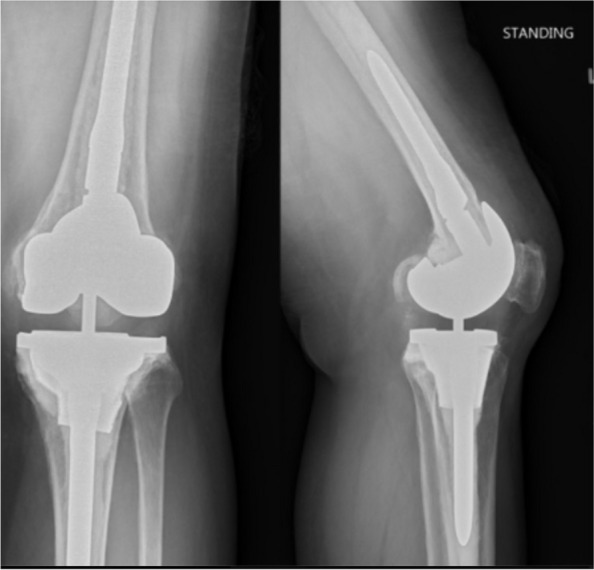

Results: Mean knee range of motion improved from 83 degrees (range 0°-120°) preoperatively to 106 degrees (range 60°-125°) postoperatively (P < 0.001). Mean KSS improved significantly from 29 (range 0-70) to 69 (range 5-100) (P < 0.001). All cones were osteointegrated. One case had transient end-of-stem pain, two developed intraoperative minor femoral fractures and one suffered from recurrent infection that did not require cone revision. Cone revision-free survivorship was 100%. There was no aseptic loosening.

Conclusions: The second-generation cone implanted with free-hand burring bone preparation yielded promising short-term outcomes in Asian knees.